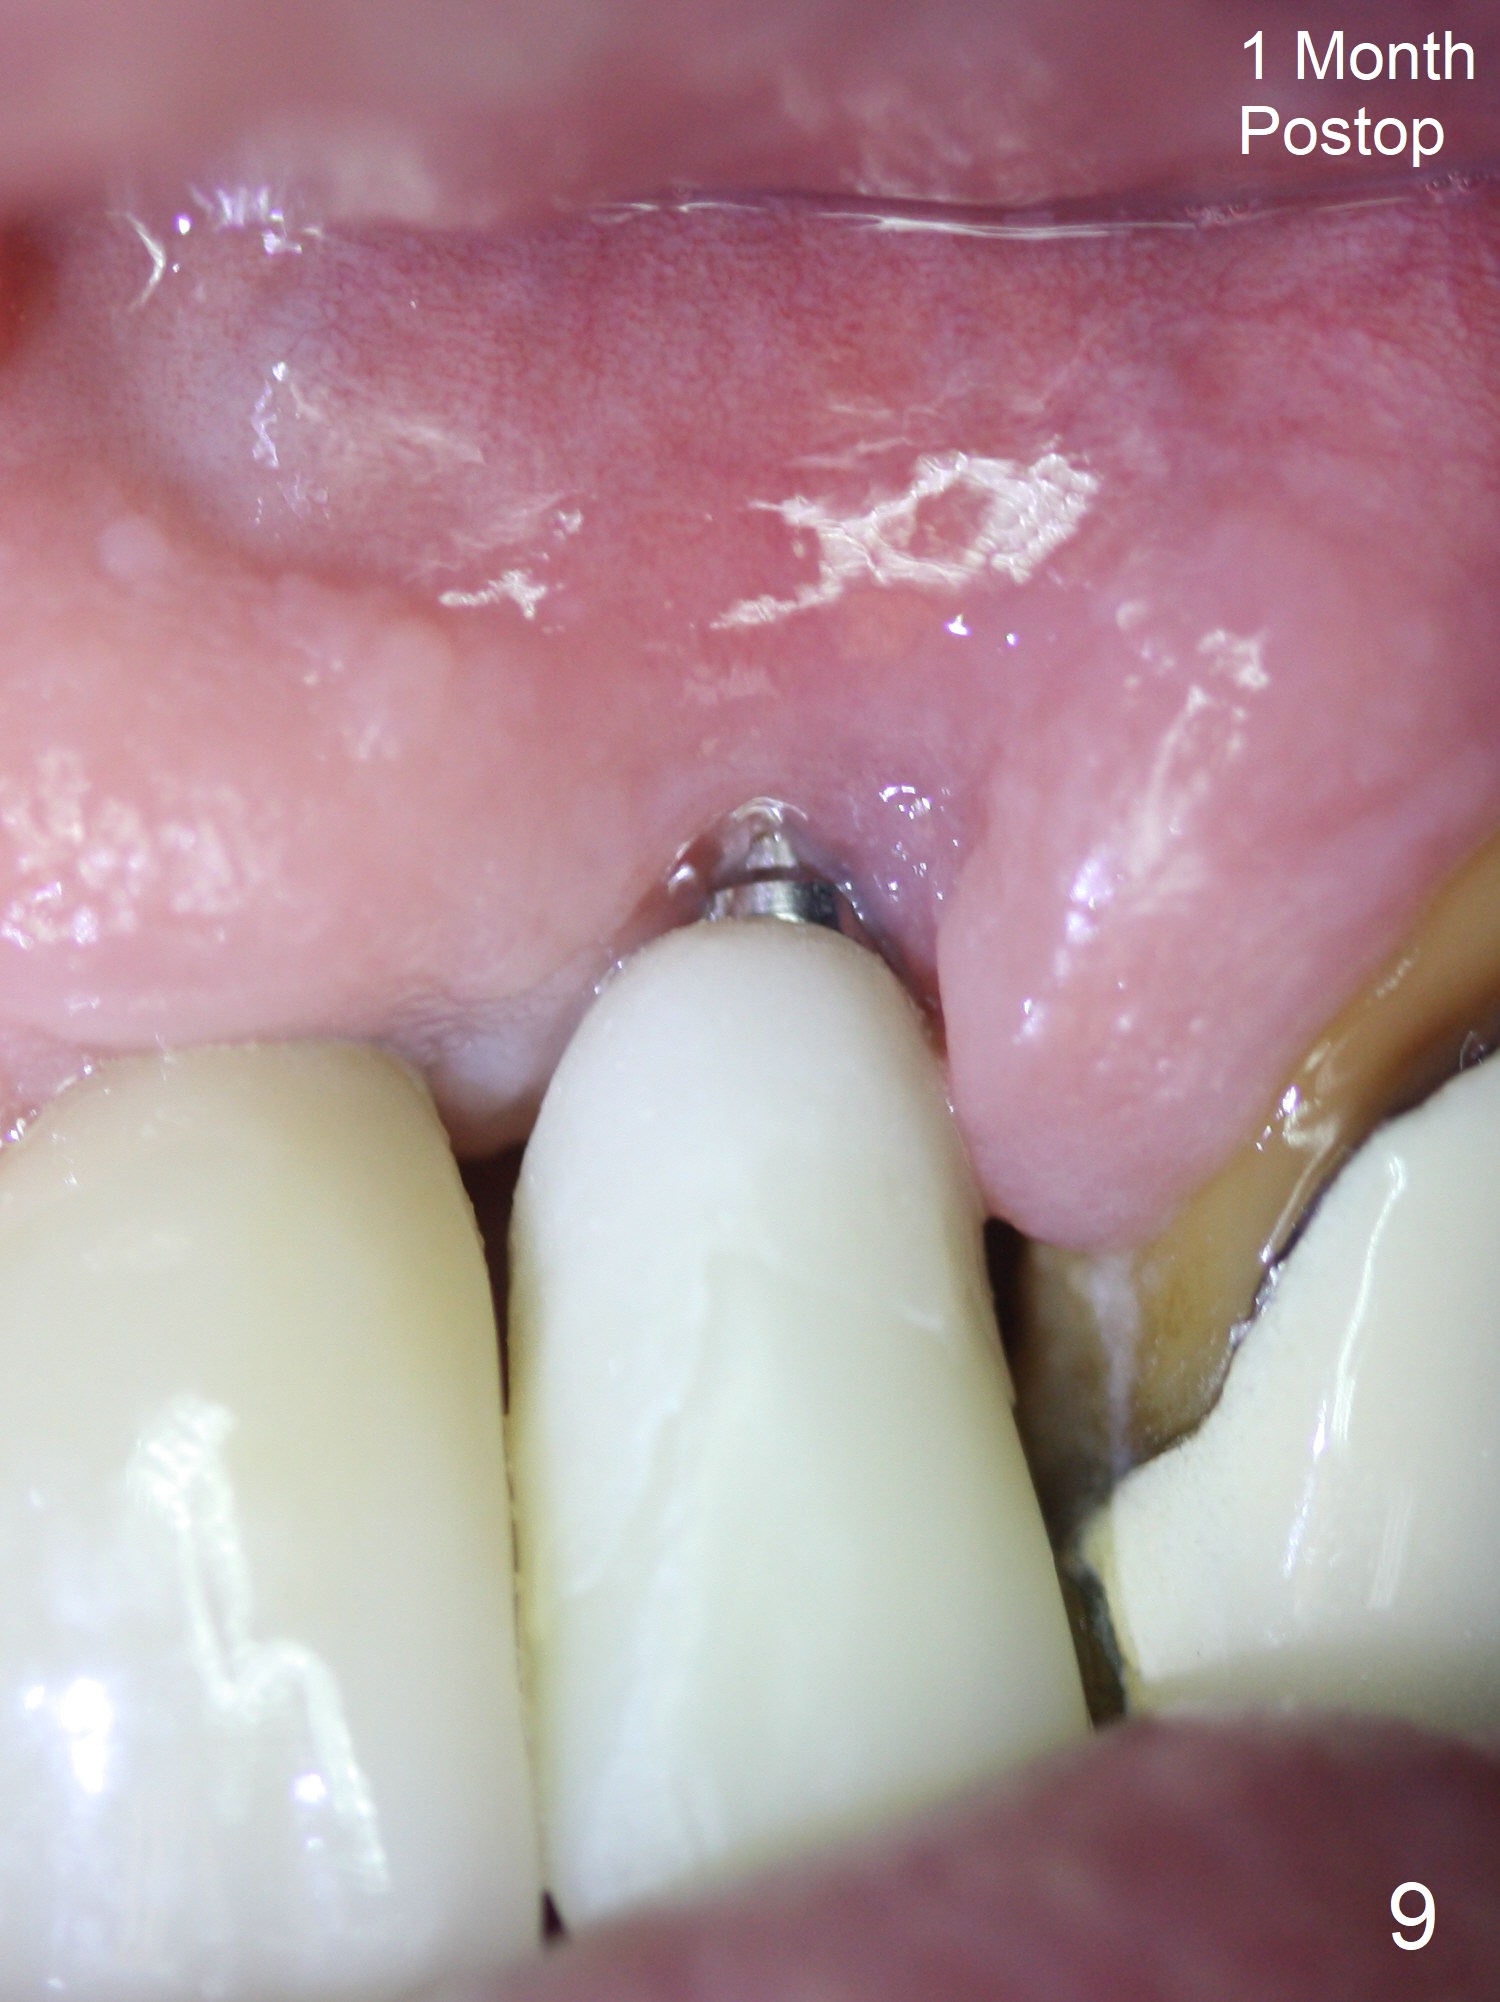

The tooth #10 has severe gingival recession (Fig.1) with loss of the buccal plate (Fig.2 *). After the initial osteotomy depth (Fig.3) increases by 2 mm, a 2.5x14(2) mm 1-piece implant is placed with insertion torque >60 Ncm (Fig.4). Palpation indicates the native bone apparently wider than CT shows. There is no sign of buccal or palatal plate perforation by palpation during osteotomy or implant placement. Vera Graft is placed repeatedly around the coronal threads (Fig.5-7 *). An immediate provisional is fabricated to close the socket (Fig.8). The buccal plate appears to collapse 1 month postop (cortical plate graft apparently more appropriate in this case); the margin of the provisional is trimmed so that the gingiva may grow incisally (Fig.9). The provisional dislodges several times postop due to short abutment. By nearly 4 months postop, the coronal bony defect seems to have been repaired (Fig.10 *). The tooth #11 has tenderness with bone loss (Fig.10 ^), corroborated by CT (distal bone loss, Fig.11 *). Since the apical bone is narrow (Fig.12), a narrow long implant is expected (Fig.13). Use an implant (3.5x13 mm) consistent with those at #14 and 15.